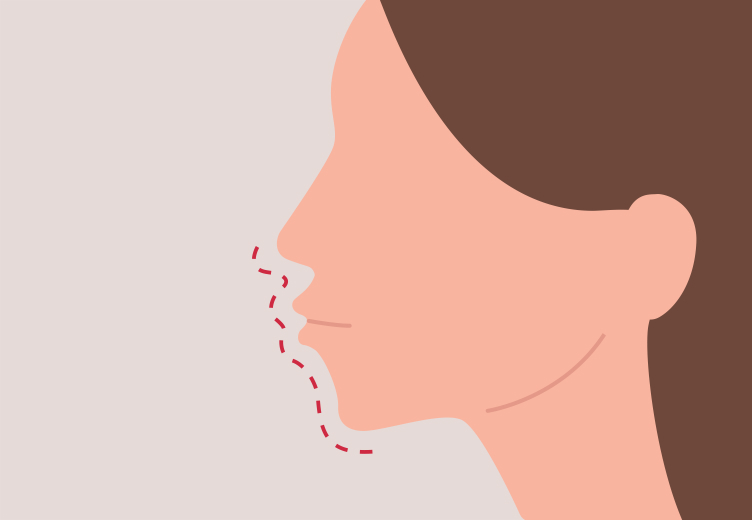

돌출입

입이나 잇몸이 많이 튀어나온 돌출입은 교정 시 앞니를 뒤로 많이 움직여야 하므로, 치아 2~4개 정도를 발치하여 안쪽으로 치아를 이동합니다.